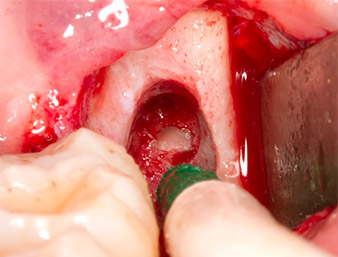

After block and local anaesthesia, the operating site was opened up and the soft tissue exposed for buccal retromolar access (Fig. 3).

The tissue above the root remnant was not completely ossified and consisted for the most part of granulation tissue modified by inflammation (Fig.4).